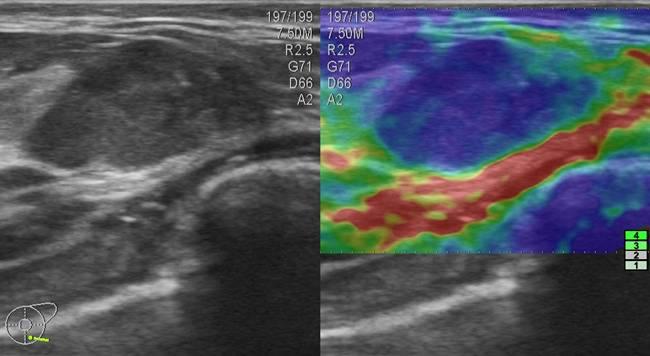

Ung thư vú - Ảnh 2

Ung thư vú

» Thông tin: Nữ giới – 33 tuổi.

» Lâm sàng: Khối tuyến vú.